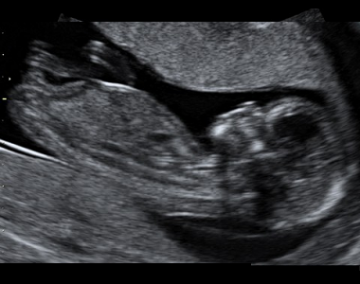

15. týden těhotenství pokračuje rychlý růst tělíčka plodu do délky. Na konci 4. měsíce tvoří hlavička asi třetinu celkové délky plodu. Mozek pokračuje ve svém vývoji. Na jeho povrchu se již vytvořila tenká vrstvička šedé hmoty.

Na povrchu hlavičky začíná být patrná část porostlá vlasy. Na okrajích očních víček se objevují jemné řasy. Oční víčka jsou stále srostlá.

Boltec ouška má už v podstatě definitivní tvar.

Celé tělíčko je pokryté velmi tenkou pokožkou. Jsou v ní již založeny všechny obvyklé vrstvy. Objevují se první buňky, které obsahují pigment. Jejich množení patří k faktorům, které v budoucnu ovlivní zbarvení kůže. Celý povrch těla je pokryt velmi jemnými kožními chloupky (lanugo).

V 15. týdnu těhotenství plod měří od temene k zadečku 9 - 10 cm, váží asi 40 – 50 g.